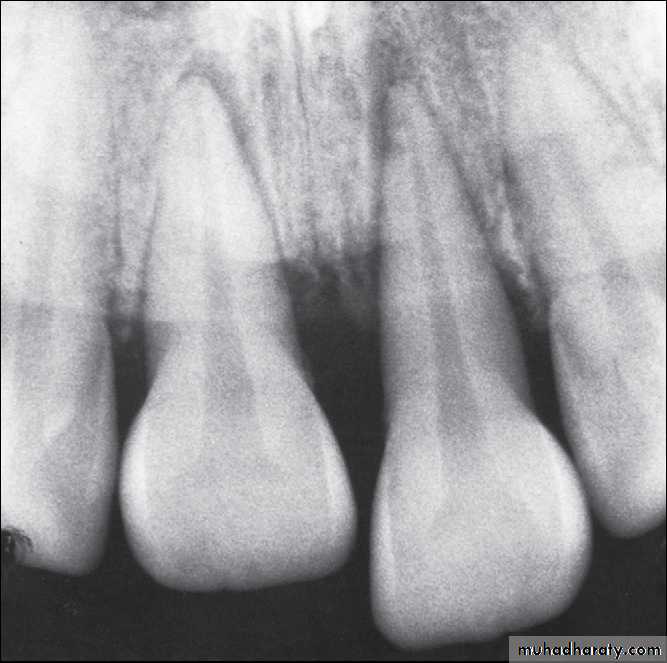

Radiographs of extruded tooth before and after repositioning and stabilization with acid-etch composite technique.